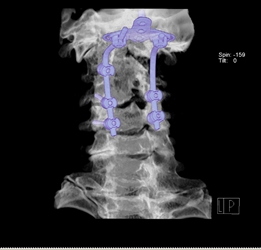

圖2示患者術(shù)后枕骨與頸椎體固定良好。